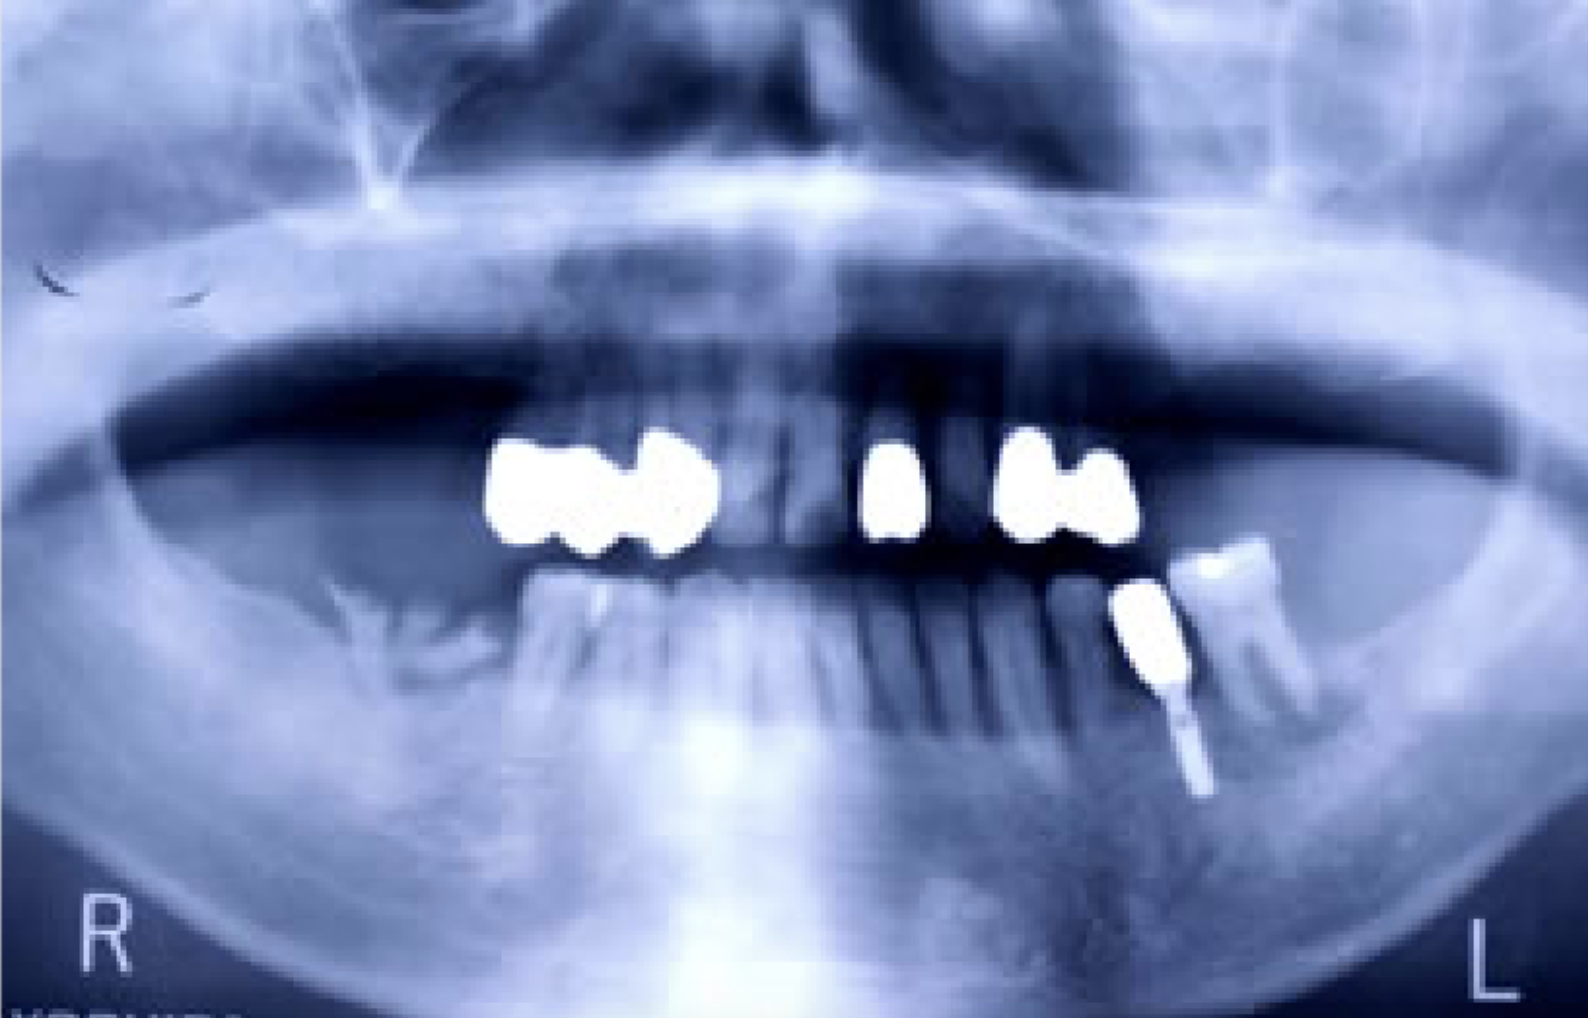

人工歯根と接合するアバットメントを示します。

抜歯後、歯周病処置、歯内療法処置、咬合高径改善、プロビジュナルレストレーションを経て最終補綴をおこないました。